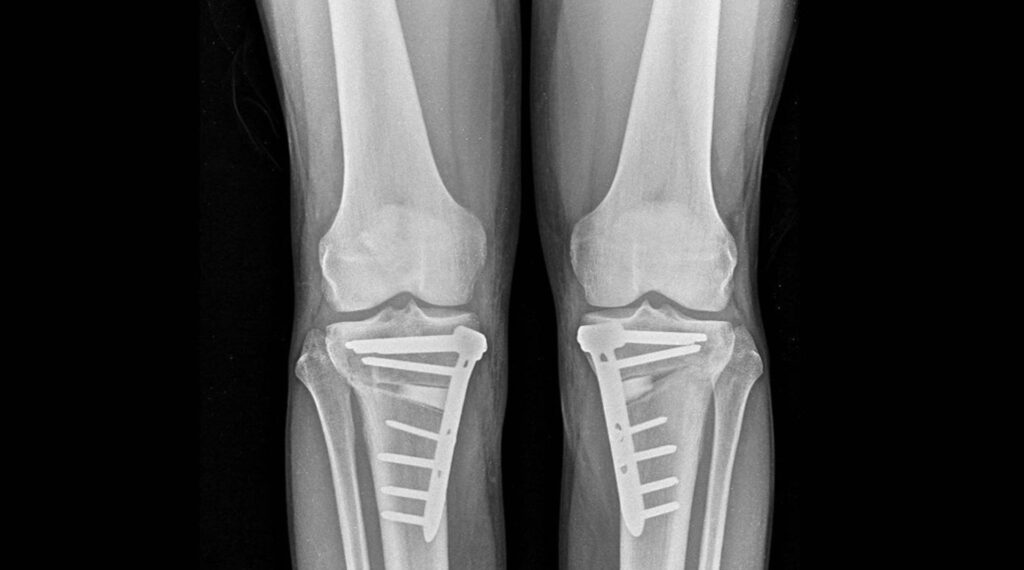

Esta intervención corrige anomalías en las piernas como el ‘genu varo’, que causa una curvatura externa de las rodillas, y el ‘genu valgo’, que provoca una forma en ‘X’ de las piernas, conservando la articulación natural y combatiendo la progresión de la artrosis sin recurrir a implantes protésicos.

La técnica de la osteotomía se lleva a cabo mediante un corte preciso en el hueso (tibia o fémur) para ajustar la carga en la pierna, redistribuyendo el peso sobre la articulación y mitigando el dolor. El doctor Arnal ha destacado la transformación de esta técnica debido a avances como la planificación digital tridimensional y nuevos sistemas de fijación e implantes. “Hoy podemos planificar en el ordenador la corrección exacta y, si lo deseamos, imprimir en 3D guías quirúrgicas personalizadas. Además, los nuevos sistemas de fijación permiten que el paciente empiece a apoyar la pierna a las 24 horas”, explicó.